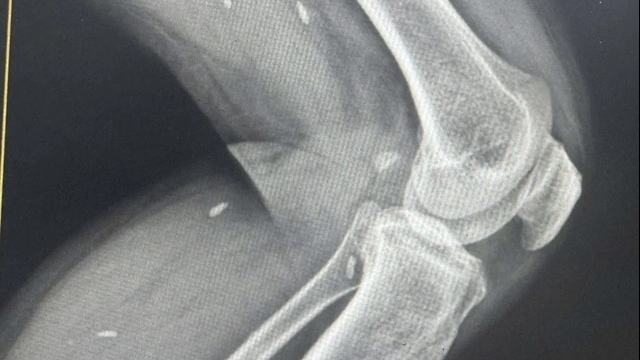

Vụ việc xảy ra tại BV đa khoa Quảng Ngãi. Bệnh nhân Nguyễn Kỷ (54 tuổi) ngụ ở xã Tịnh Hà (Sơn Tịnh) nhập viện ngày 14/8. Đến ngày 21/8, bệnh nhân được chỉ định phẫu thuật lấy sỏi đường tiết niệu bên trái.

Sau phẫu thuật khoảng 6 tiếng, bệnh nhân Kỷ được đưa về khoa Ngoại tổng hợp. Người nhà bệnh nhân được thông báo ca mổ thành công, sức khỏe bệnh nhân dần ổn định.